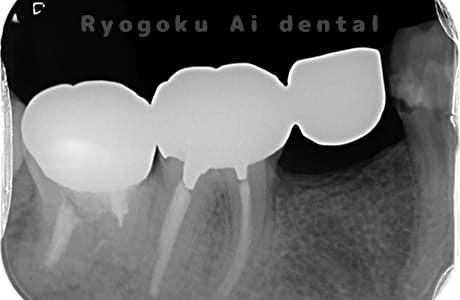

Case03

- 重度カリエス、慢性根尖性歯周炎

- 治療内容

- 自家歯牙移植

- 治療費用

- 220,000円

他院で右下の根の治療を行い、セラミックを被せる説明をされていたが、根の治療が終わらないため転院された患者さんです。隣の親知らずの抜歯の必要性と、根の治療を行なっている歯牙の予後が悪いため、移植治療を提案し、右下の親知らずの抜歯と同時に、右下の奥歯(7番)への移植治療を行いました。被せ物を行う必要もなく、順調に経過してます。